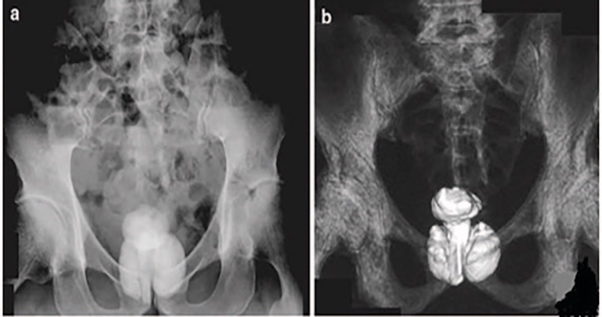

Рис.1. Камни простаты: А – на регнтгенографии. Б – на компьютерной томографии.